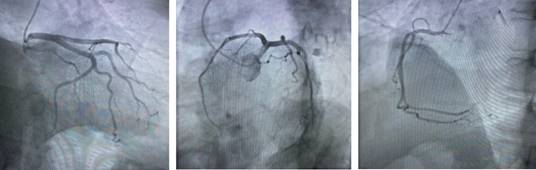

The antithrombotic treatment was initiated (aspirin, clopidogrel and anticoagulation with enoxaparin), atorvastatin, metoprolol and enalapril as part of the protocol established by NSTEMI management guidelines. Diagnostic coronary angiography (Figure 2) was performed, in which no significant angiographic lesions were found in epicardial arteries. Once the existence of obstructive coronary lesions as the cause of the myocardial injury had been ruled out, cardiac magnetic resonance imaging was performed (Figure 3). The process of acute myocarditis was observed, and a preserved biventricular function; myocardial ischemia was discarded.

Figure 2: Coronary angiography. Coronary arteries without significant stenosis, thrombolysis in myocardial infarction (TIMI) 3 flow.